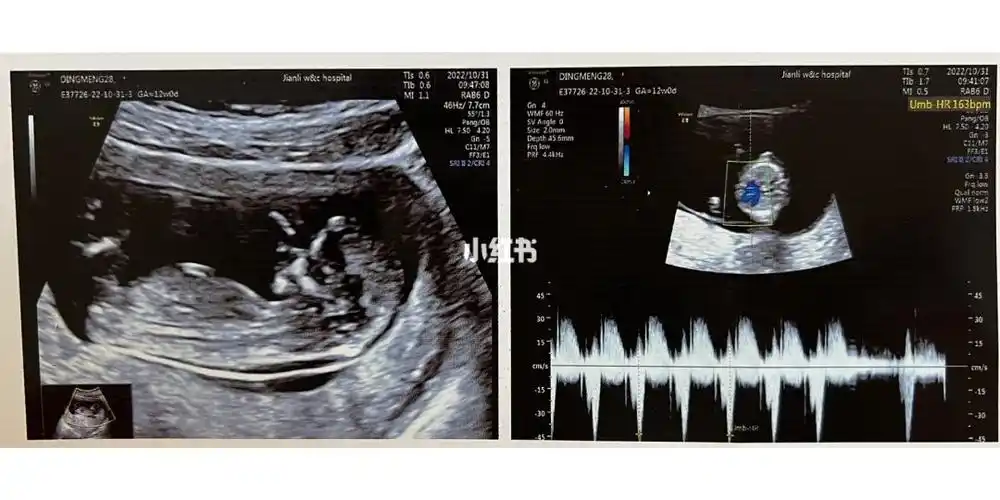

nt检查宝宝很配合但数值20mm